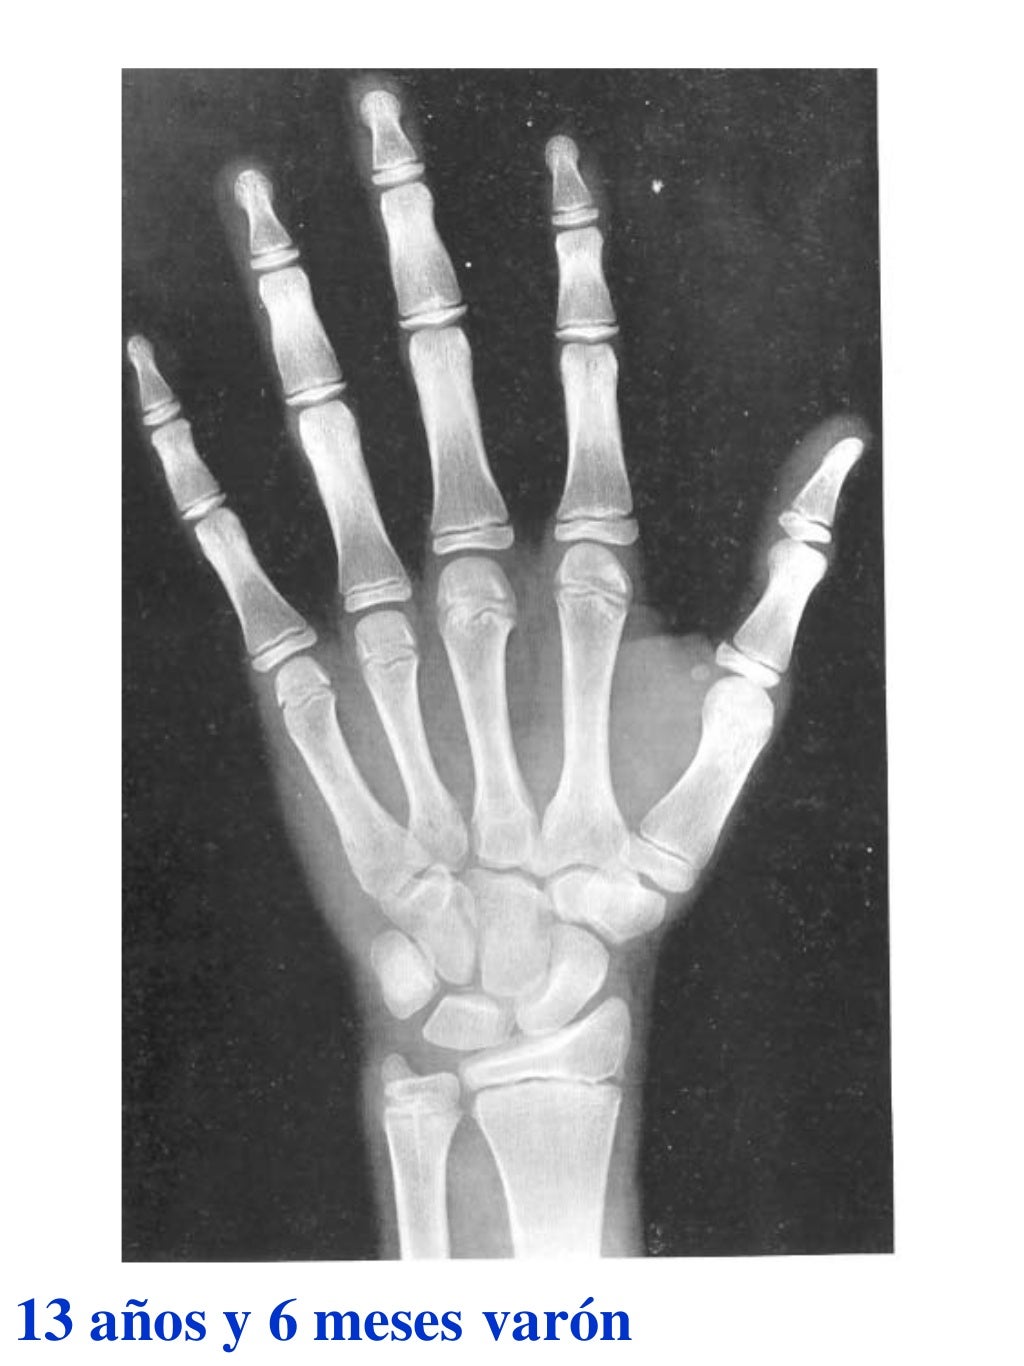

Tablas De Greulich Y Pyle . Scribd is the world's largest social reading and publishing site. This systematic review summarizes the. The radiographic atlas of skeletal development of the hand and wrist by ww greulich and si pyle is a classic radiological. The standards established by greulich and pyle, undoubtedly the most popular method, consist of two series of standard plates. The greulich and pyle method is one of the two main ways to assess the bone age of children. El documento lista las edades. Both main methods of bone age. 153 recomendaciones • 616,869 vistas. Atlas greulich y pyle | pdf | descarga gratuita. The greulich and pyle atlas is used to estimate the age of children and adolescents.

Tablas De Greulich Y Pyle The standards established by greulich and pyle, undoubtedly the most popular method, consist of two series of standard plates. The standards established by greulich and pyle, undoubtedly the most popular method, consist of two series of standard plates. El documento lista las edades. This systematic review summarizes the. The greulich and pyle method is one of the two main ways to assess the bone age of children. Both main methods of bone age. Scribd is the world's largest social reading and publishing site. 153 recomendaciones • 616,869 vistas. Atlas greulich y pyle | pdf | descarga gratuita. The greulich and pyle atlas is used to estimate the age of children and adolescents. The radiographic atlas of skeletal development of the hand and wrist by ww greulich and si pyle is a classic radiological.